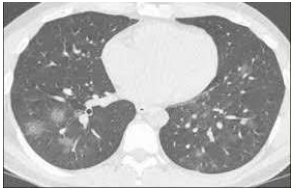

Um homem de 64 anos de idade, diabético, em uso regular de suas medicações, procurou um pronto-socorro na cidade de São Paulo no dia 24 de junho de 2020, referindo que, há seis dias, vinha com dor de garganta e diarreia, sendo que, há três dias, iniciou tosse seca. Ao ser questionado pelo médico, ainda relatou que teve perda de apetite dois dias antes do início dos sintomas. O paciente levou consigo hemograma e urina tipo 1 de uma passagem que tivera, há dois dias, em outro serviço médico, com resultados normais. Negou tabagismo, etilismo ou exposição a trabalhos que, ao longo da vida, pudessem ter desencadeado doenças profissionais. Ao exame físico, apresentava bom nível de consciência,saturação de O2 de 85% em ar ambiente e de 97% com cateter de O2 2L/min., FC de 95 bpm, 37,8 ⁰C de temperatura, PA de 145 x 90 mmHg, FR de 18 irpm, obesidade grau II e encontrava-se prostrado, desidratado, corado, anictérico e com movimentos respiratórios amplos. Aparelho cardiovascular com bulhas rítmicas, sem sopro, e tempo de enchimento capilar igual a 4 s. Aparelho respiratório com murmúrio vesicular difuso mais evidente em bases pulmonares, bilateralmente. Som pulmonar claro. Abdome com hiperdinamia à ausculta, ausência de massas à palpação superficial e profunda e dor difusa discreta. Exames atuais com Hb 16, Ht 54, leucócitos 12.000 (73% neutrófilos e 25% linfócitos), plaquetas 285.000, Na 158, K 2.5, Mg 1.9, ureia 80 e creatinina 2.5. Gasometria em ar ambiente com pH 7.3, PaO2 58 mmHg, PaCO2 40 mmHg, BE –4, lactato arterial 1.25, bicarbonato 17, CPK 350, ALT 70 e AST 60. Urina I com densidade 1.030, proteína +++, glicose +++, leucócitos 250.000 e eritrócitos 500.000. Realizou, também, a tomografia de tórax mostrada a seguir.

Com base nessa situação hipotética, assinale a alternativa correta quanto à conduta mais segura para o paciente.